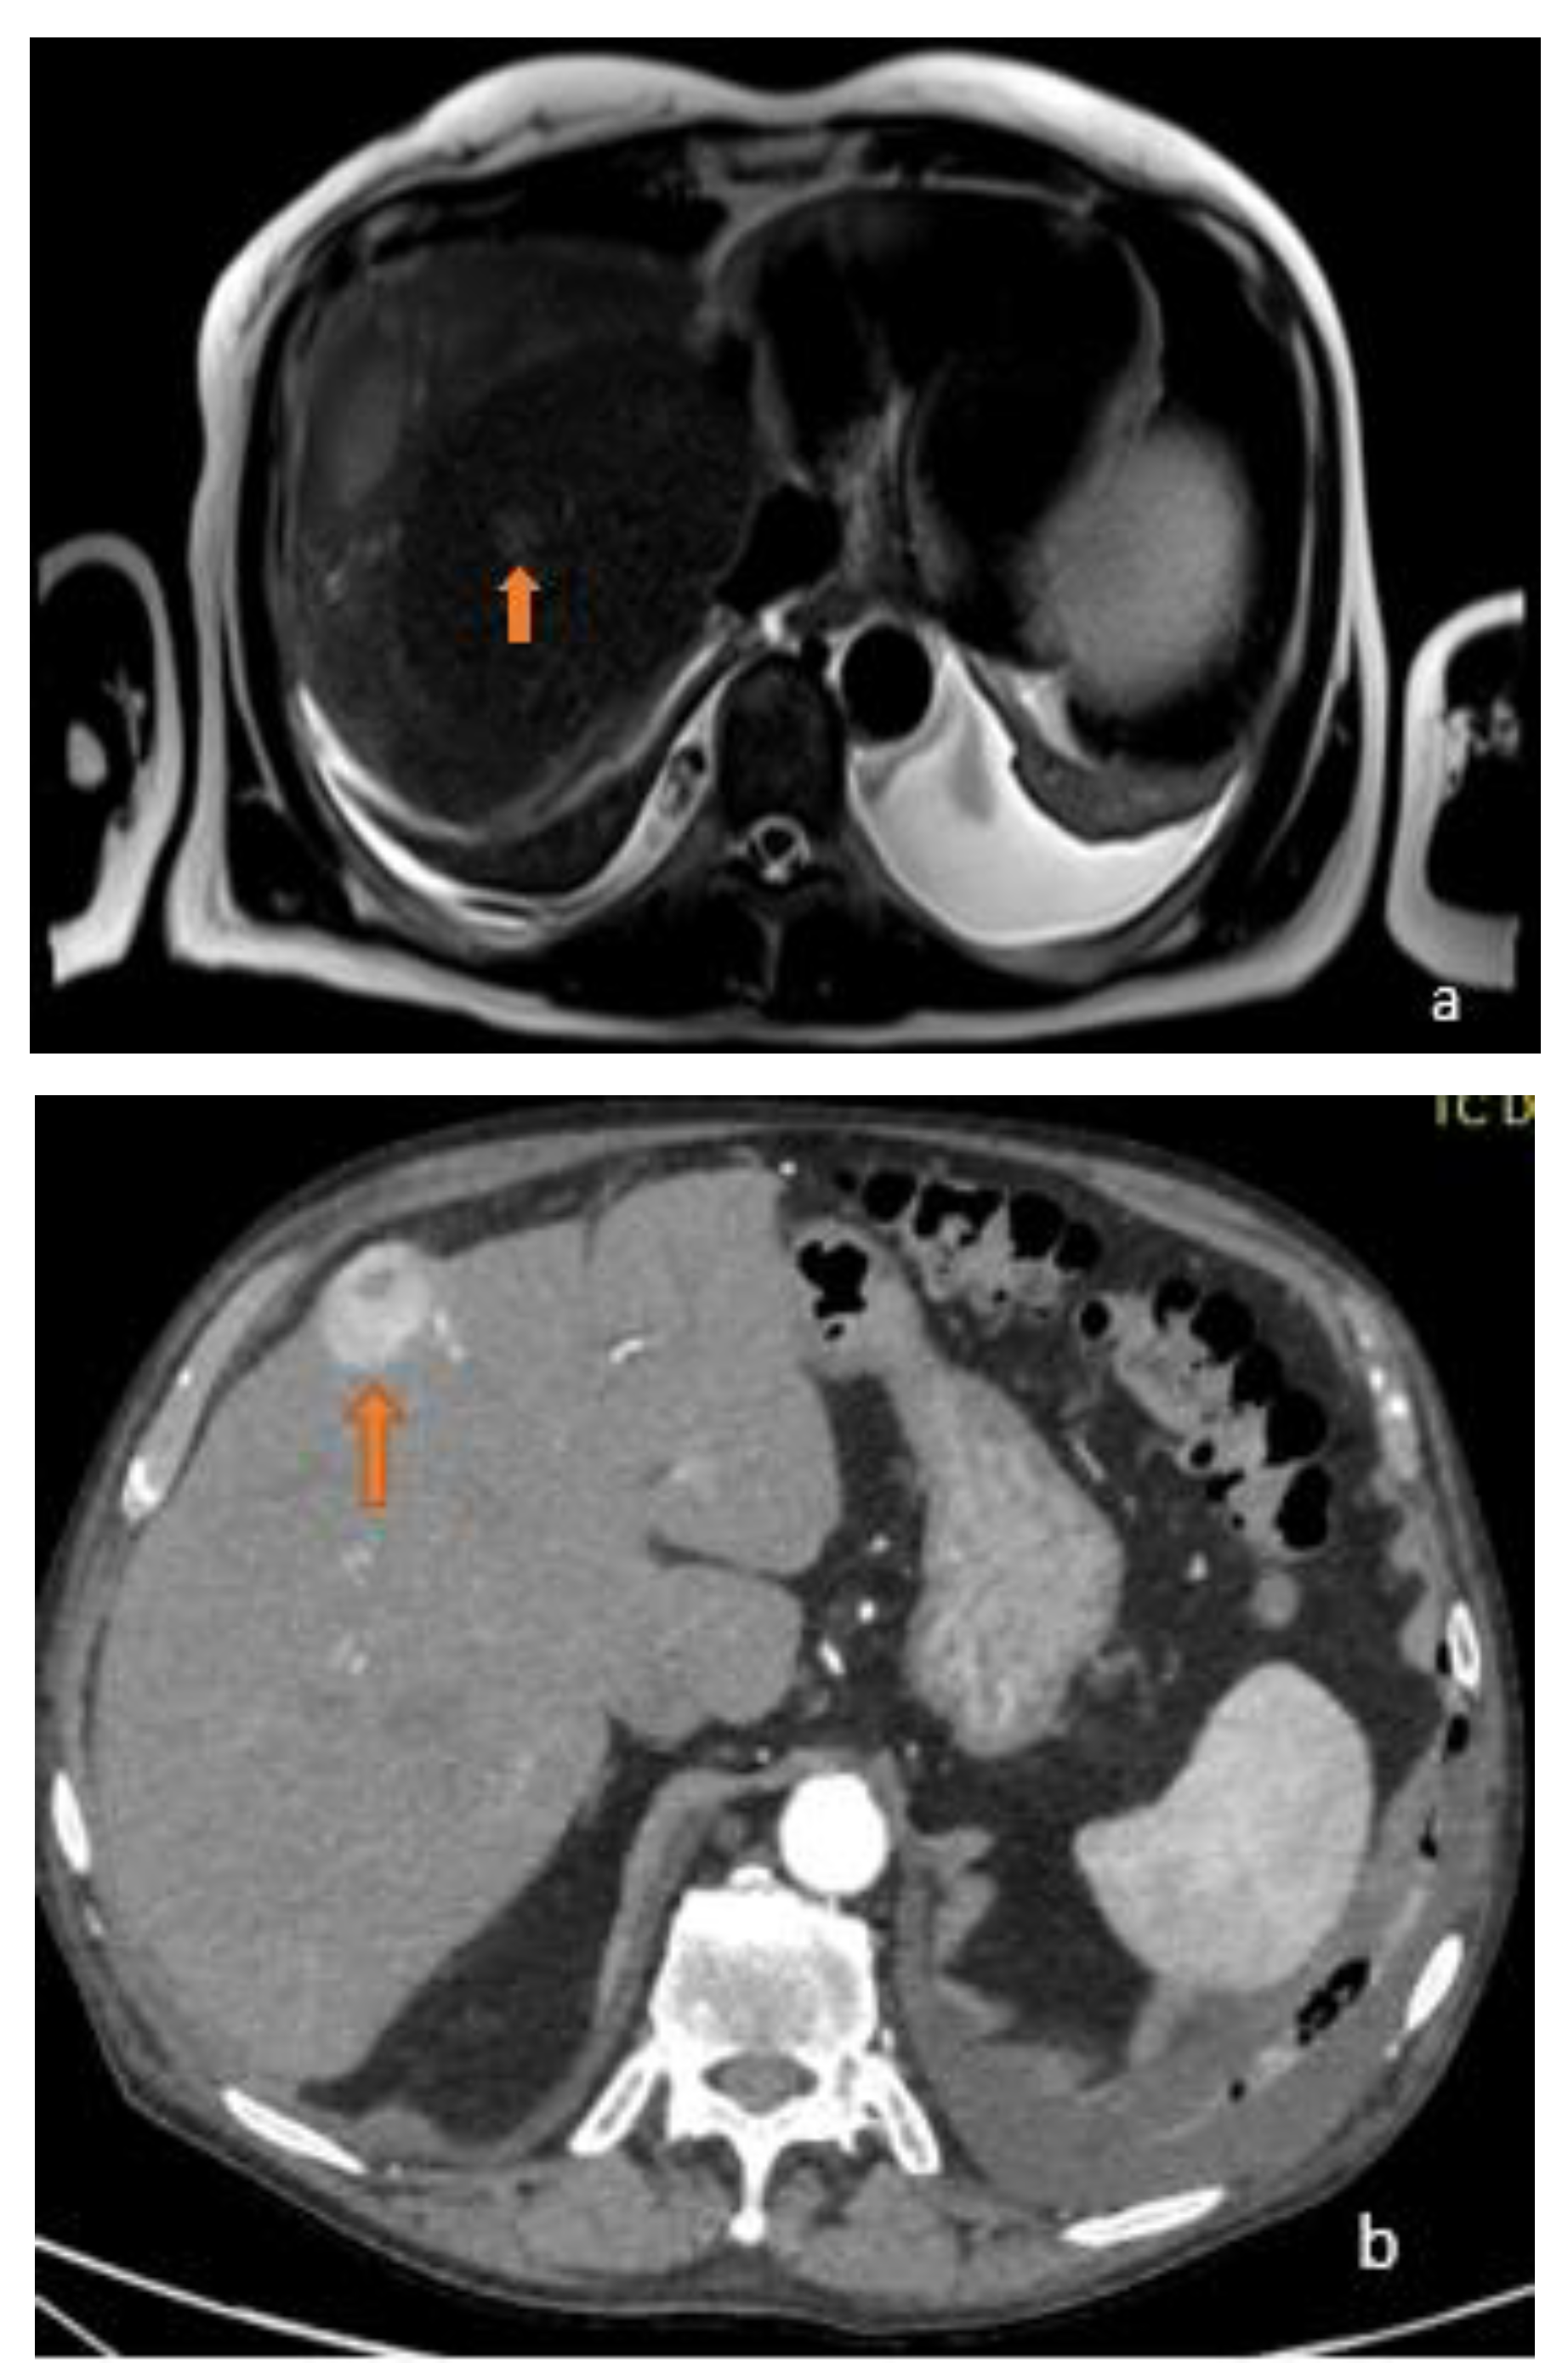

3.1. FLL Feature Characteristic

5.1. FLL Feature Characteristic